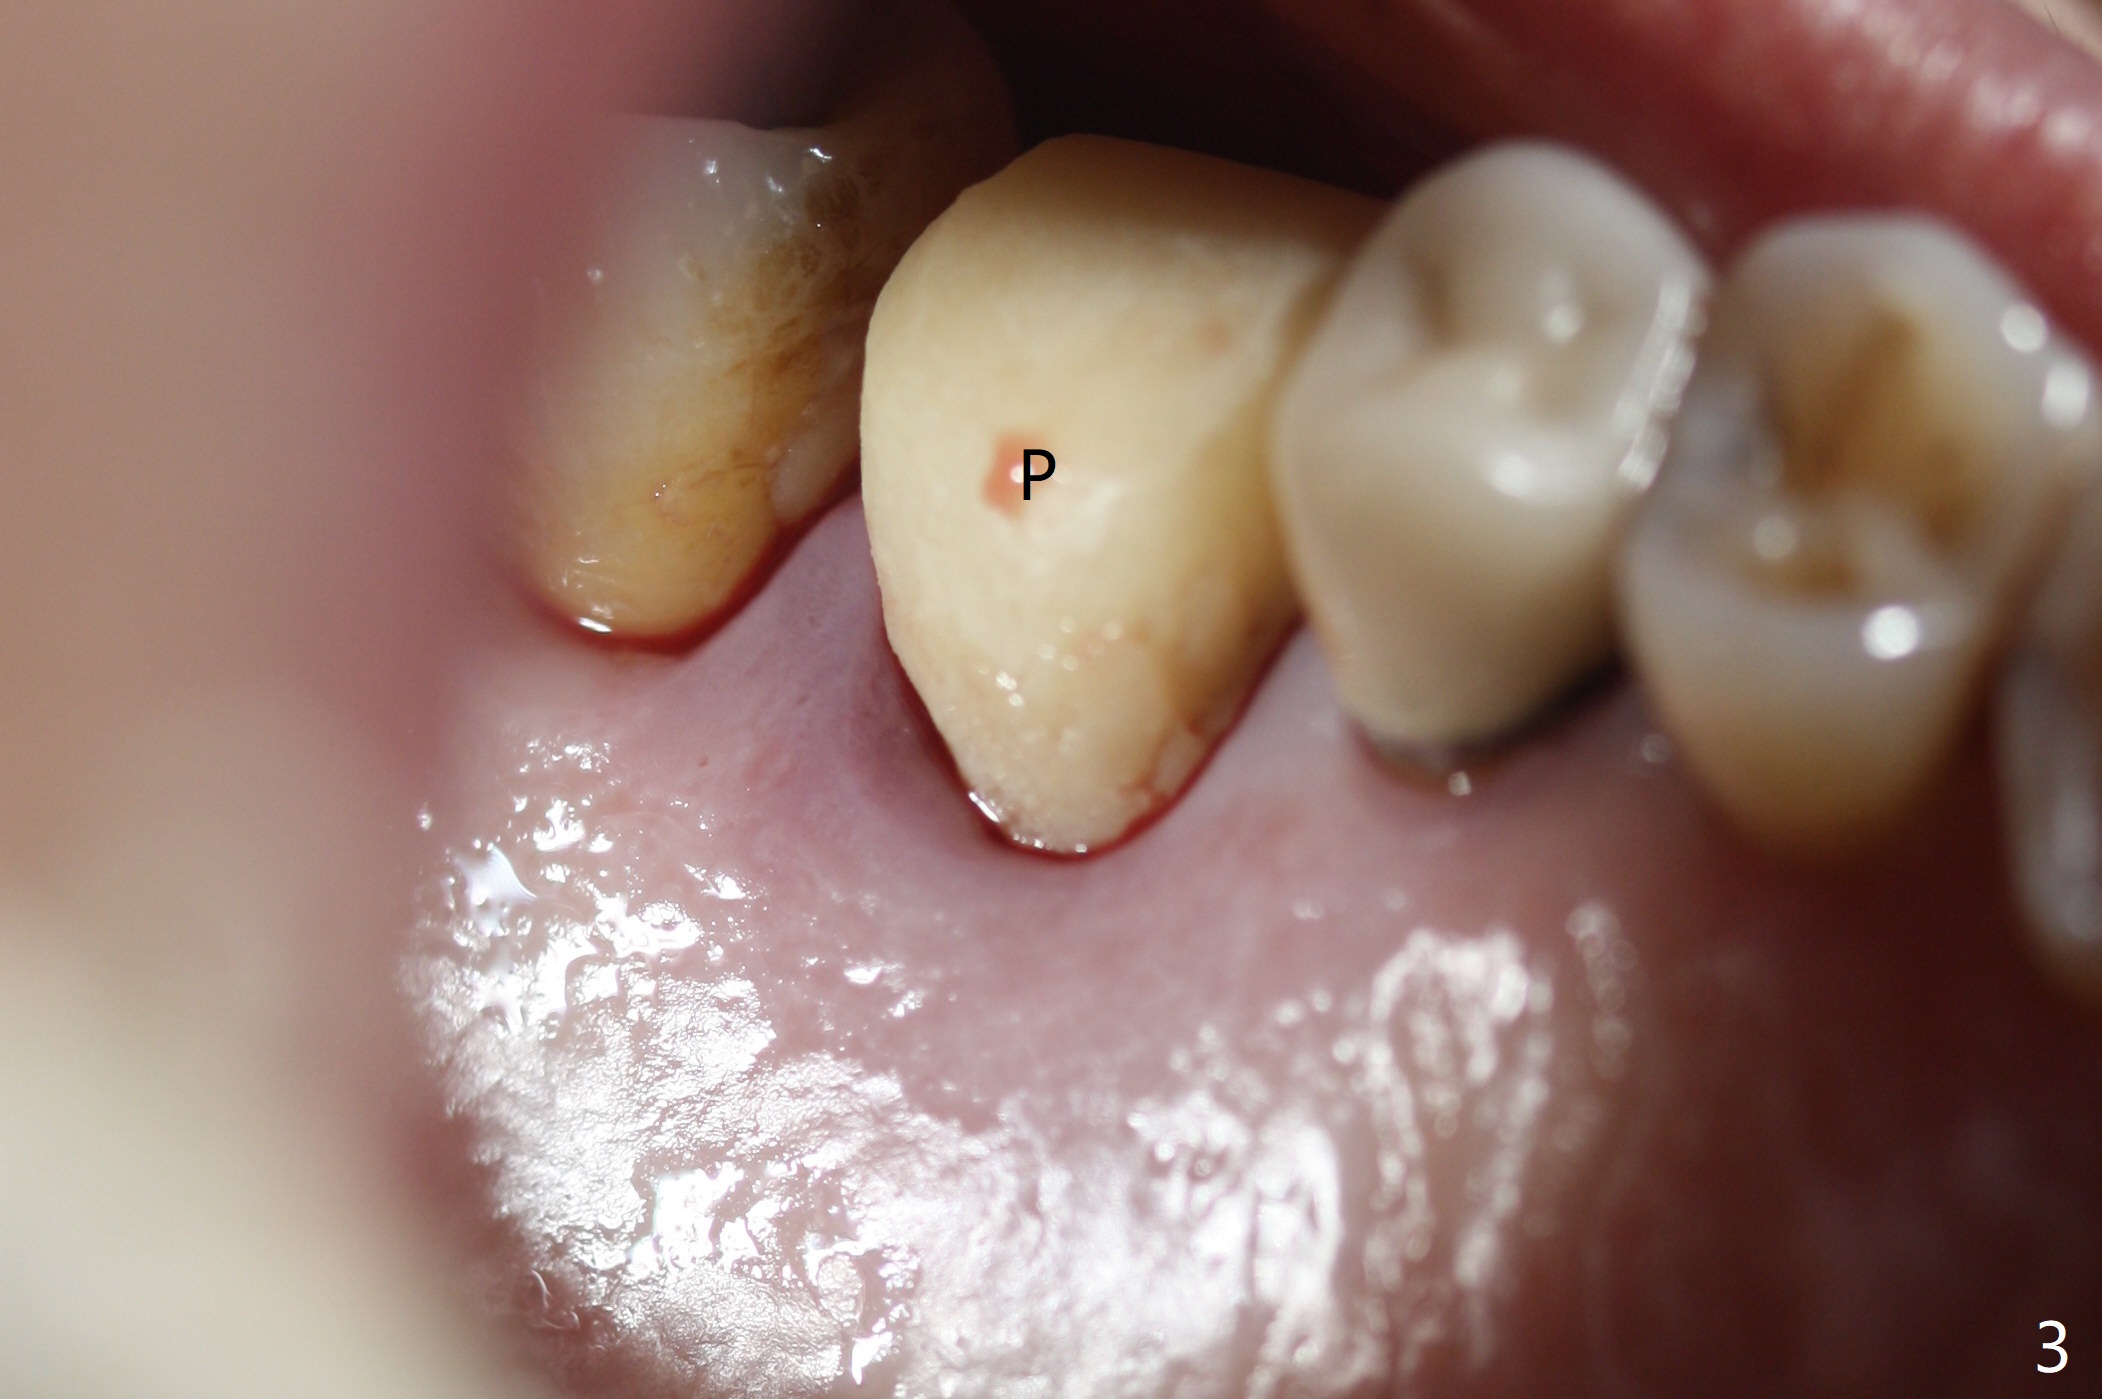

A 5x10 mm implant is placed at #3 according to drill sequence except 4.5x10 mm drill having to be used (plan: underdrilling using 4.0x10 mm as the last one) because of dense bone. Insertion torque is >50 Ncm. Although the implant apparently penetrates the sinus floor (Fig.1), the bottom of the osteotomy is intact before implant placement. In addition, the 12 mm bone trimmer does not touch the septal bone, while 2.2x8.5 mm drill starting to remove bone. In spite of using the largest cementation abutment (6.5 mm), the buccal (Fig.2) and palatal sockets with bone graft (*) are exposed. An immediate provisional (Fig.3 P) is fabricated for remaining socket closure. The buccal gingiva appears to have receded relative to the abutment margin nearly 4 months postop (Fig.4). The mesial crestal bone defect seems to be repairing (Fig.5 (*),6). The abutment later changes to a 5.7x5.5(2) mm one with margin modification buccomesiolingually before impression.